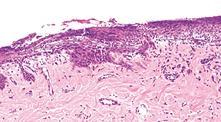

Pemphigus vulgaris, skin, dog. A, Suprabasilar clefting has left a row of basal cells (arrows) attached to the dermis. The single row of basal cells is fragile and easily damaged leading to formation of ulcers, with subsequent fluid loss and secondary bacterial infection. H&E stain.

B, Leg. Note the erythema and large confluent areas of ulceration. In contrast to pemphigus foliaceous (more commonly characterized by erosions and crusts), pemphigus vulgaris is characterized by larger more confluent ulcers because the acantholysis in pemphigus vulgaris occurs deeper in the epidermis (in the cells of the lower epidermis). Vesicles are not frequently seen as they rapidly progress to ulcers, the more common clinical lesion.